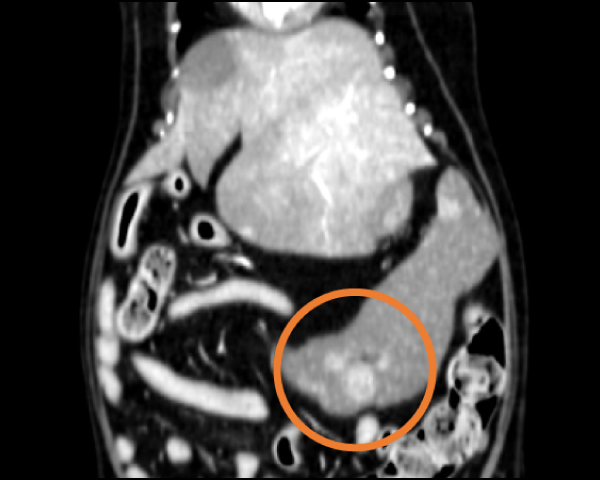

造影CT検査にて腫瘤の浸潤を評価